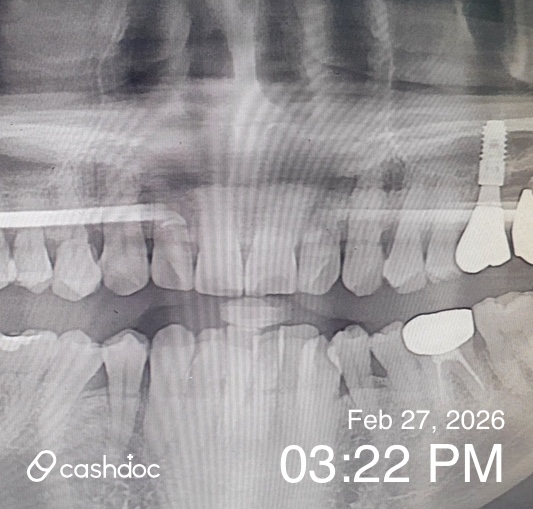

임플란트.이식이 필요하다고 진료받고 강남에서 나름 유명하다고 하고 블로그에서 괜찮다고 소개하여 집에서 멀지만 치료받게 되었어요

어느날 인공치근을 이식받고 나서 약 일주일지나 갑자기 통증이 심하고 피도 나서 이상하여 방문했더니 당시 의사가 아물기전 단순 통증일수 있으니 소염진통제 등 약처방만 하여 믿고 기다렸으나 통증이 더 심해져 재방문했더니 그제서야 픽스쳐가 흔들려 그런거라며 급하게 재이식 등 과정을 거쳤습니다!